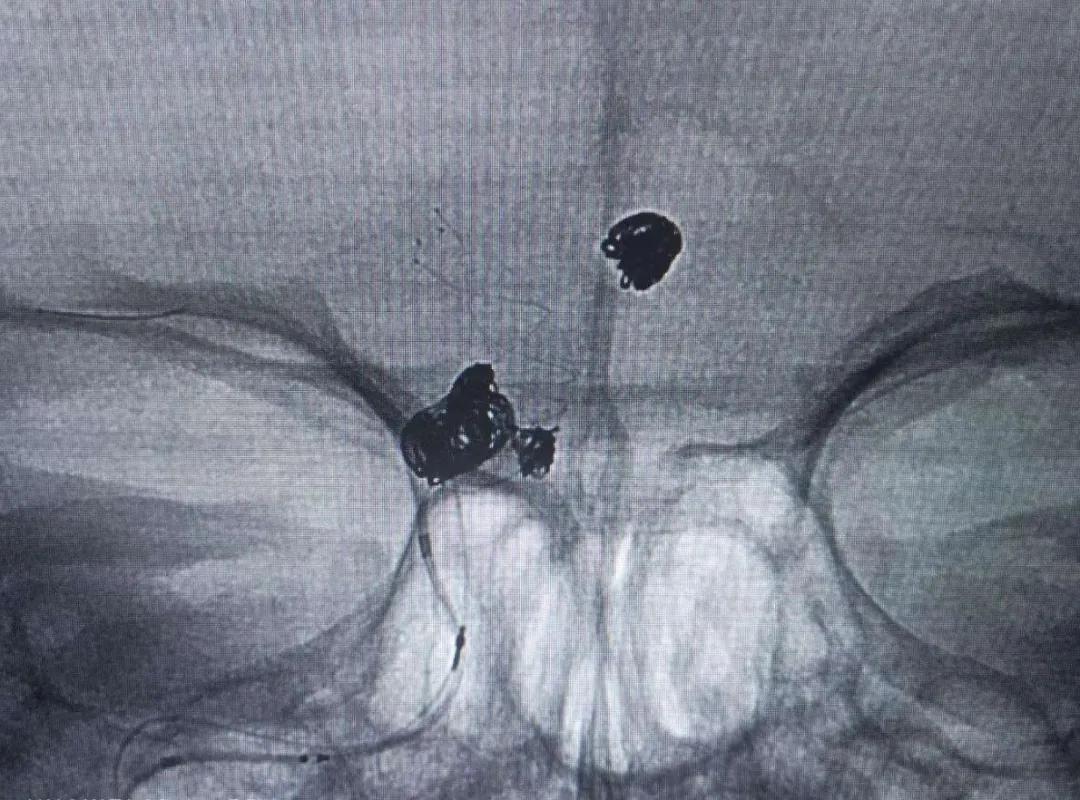

3枚动脉瘤全部栓塞成功:

完善术前检查后,钱阿姨立马被推进手术室。张世荣主任凭着丰富的临床经验和精湛的操作技术,精细操作,把微导管送入前交通动脉瘤腔内,并置入弹簧圈,致密地填塞了动脉瘤。其后,用支架辅助结合弹簧圈,将右侧颈内动脉C6段的2个动脉瘤也完美栓塞。手术耗时5个小时,术中无动脉瘤破裂出血,一次手术将颅内的3颗“*弹炸**”终于全部排除!